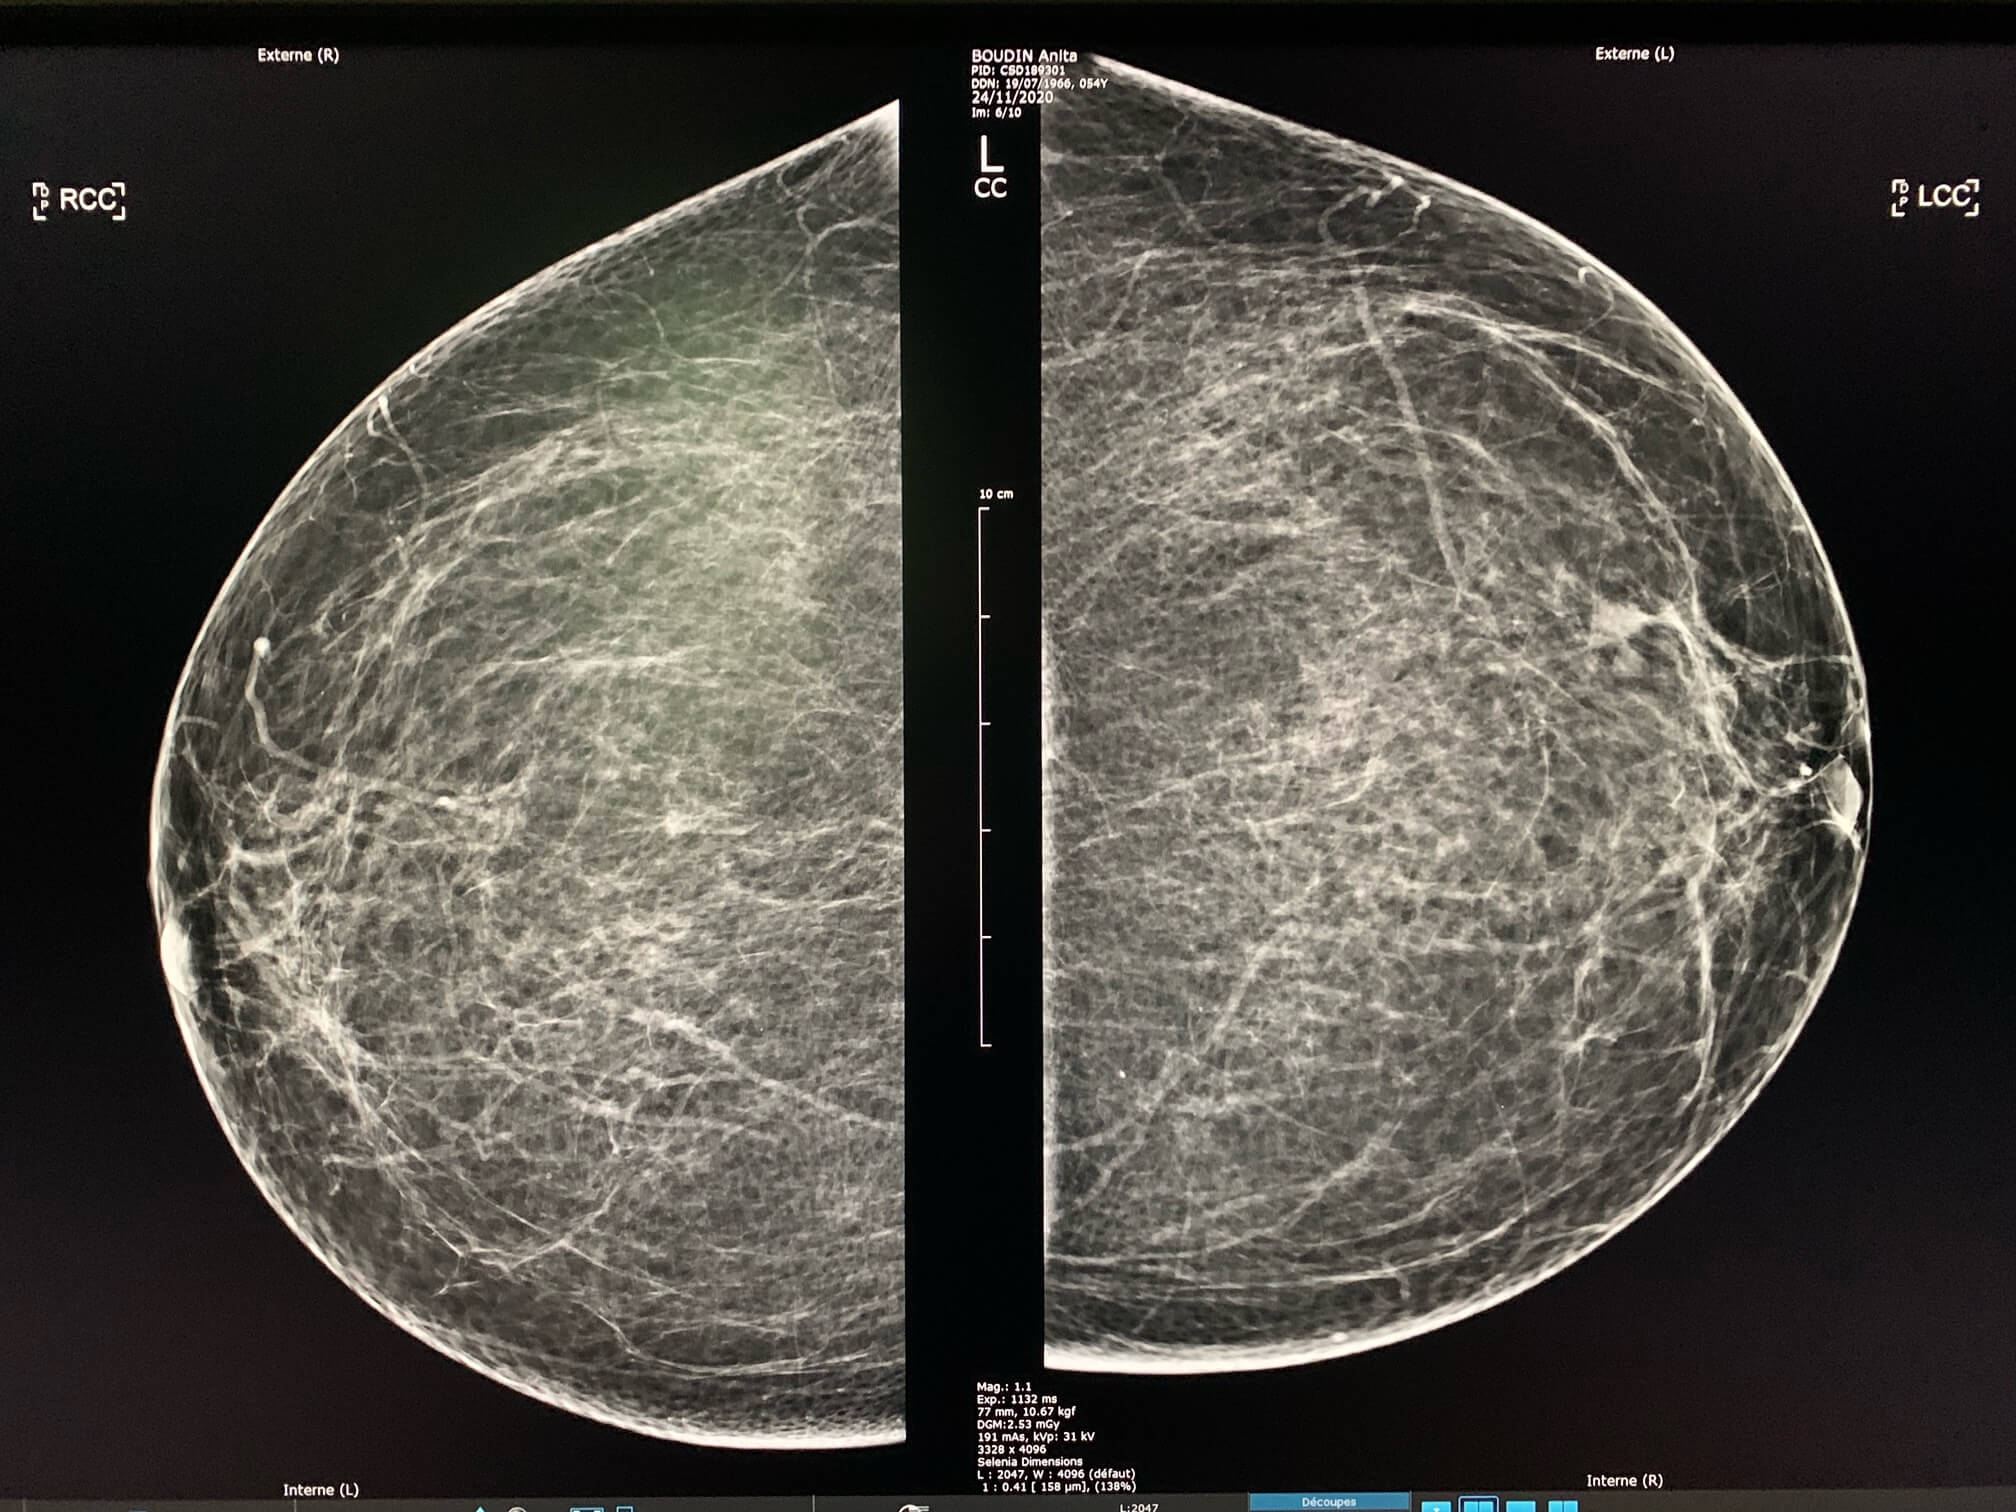

Patiente de 54 ans, mammographie de dépistage.

MammoScreen™ pointe un surcroît d’opacité du quadrant inféro-externe du sein gauche.

Un cliché localisé révèle une image a contours spiculée.

L’échographie mammaire met en évidence une formation hypoéchogène atténuante à contours irréguliers.

La biopsie mammaire retrouve un adénocarcinome infiltrant SBR II, RH+

*Cas de la pratique de Dr. Le Van An.